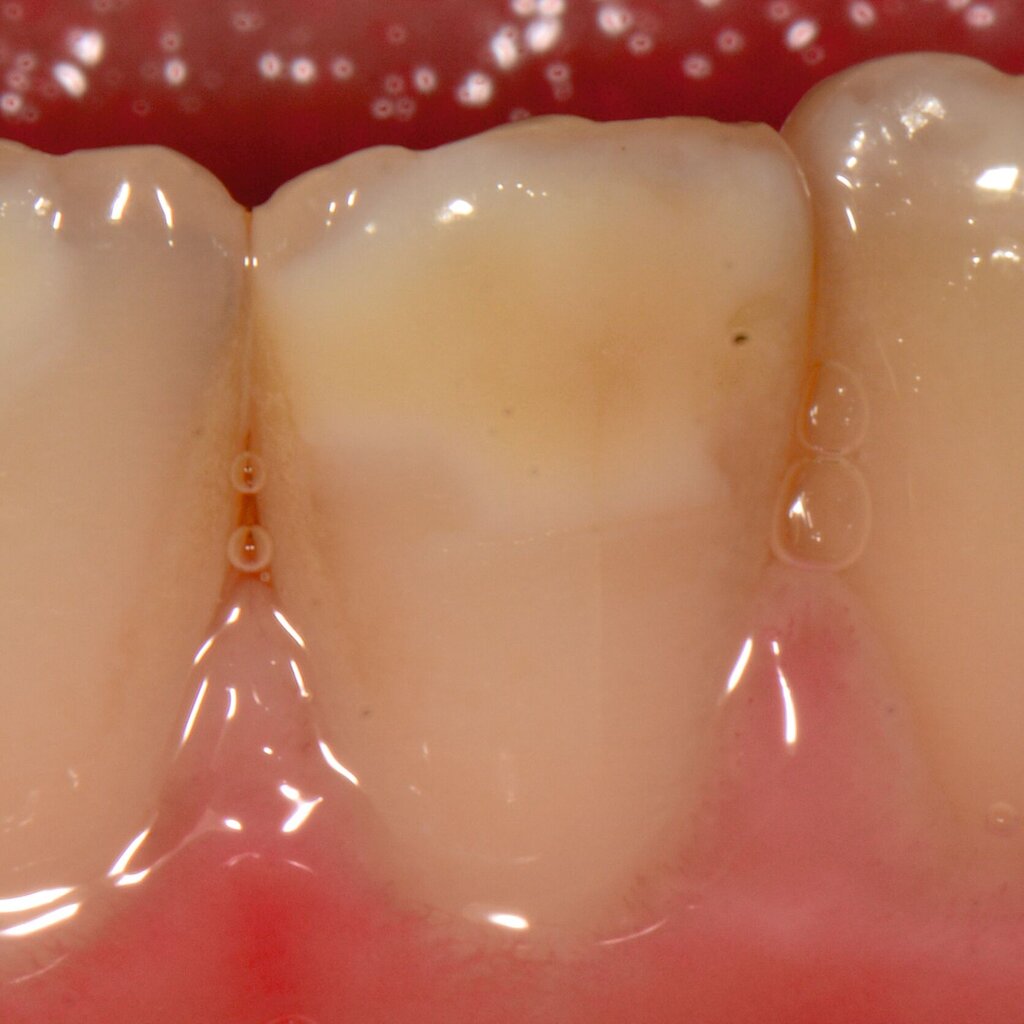

Das klinische Erscheinungsbild an bleibenden Zähnen zeigt typischerweise weißlich-gelbe bis gelblich-braune Opazitäten, die zumindest in einigen Bereichen durch eine scharfe Abgrenzung (engl.:„demarcated opacities“) zum gesunden Zahnschmelz charakterisiert sind (Abbildungen 3 und 4). Die abgegrenzten Hypomineralisationen befinden sich mehrheitlich im Bereich der inzisalen Kronenhälfte unabhängig von dem Auftreten an Front- oder Seitenzähnen. Die Ausprägung am Zahn kann dabei auf einzelne Areale oder Höcker begrenzt sein.

Die häufigste und relevanteste Differenzialdiagnose sind kariöse Läsionen. Dies trifft vor allem für kariesaktive Patienten zu, die multiple und ausgedehnte (initial)kariöse Läsionen aufweisen können. Die Differenzialdiagnostik gelingt hier auf Grundlage einer sorgfältigen klinischen Untersuchung, wobei die Lokalisation und Konfiguration wichtige diagnostische Hinweise geben. Kariöse Läsionen sind dabei typischerweise im Bereich von Plaqueretentionsstellen, zum Beispiel Gingivarand und Approximalflächen, detektierbar. Demgegenüber befinden sich Hypomineralisationen mehrheitlich im Bereich der inzisalen Kronenhälfte und damit außerhalb der Kariesprädilektionsstellen.

Eine weitere Strukturstörung ist die Dentalfluorose. Das klinische Erscheinungsbild von Fluorosen unterscheidet sich durch diffuse Opazitäten grundlegend im Vergleich zu den scharf begrenzten Opazitäten der MIH-Zähne. Fluorosen treten symmetrisch und möglicherweise an allen Zähnen infolge einer langfristigen Fluoridüberdosierung auf. Genetisch bedingte Erkrankungen der Zähne, wie Amelogenesis imperfecta und Dentinogenesis imperfecta, werden durch spezifische Genmutationen verursacht und sind dadurch gekennzeichnet, dass alle Zähne beider Dentitionen gleichermaßen betroffen sind [Kühnisch et al., 2025; DGKIZ et al., 2024]. Im Gegensatz dazu sind MIH-Defekte mehrheitlich an den sogenannten Indexzähnen zu finden. Zudem ist oftmals ein symmetrisches Auftreten zu beobachten.